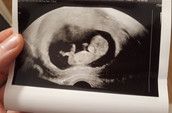

Dem Kleinen geht es super, er ist aber ein eher zierliches Kind, der Bauchumfang ist immer im unteren Bereich und der schwerste ist er auch nicht gerade, deswegen wird das jetzt immer im Ultraschall kontrolliert (zuletzt wurde er Dienstag auf 2500g geschätzt) . Aber er wächst und nimmt gut zu, deswegen ist das wohl okay so. 😅